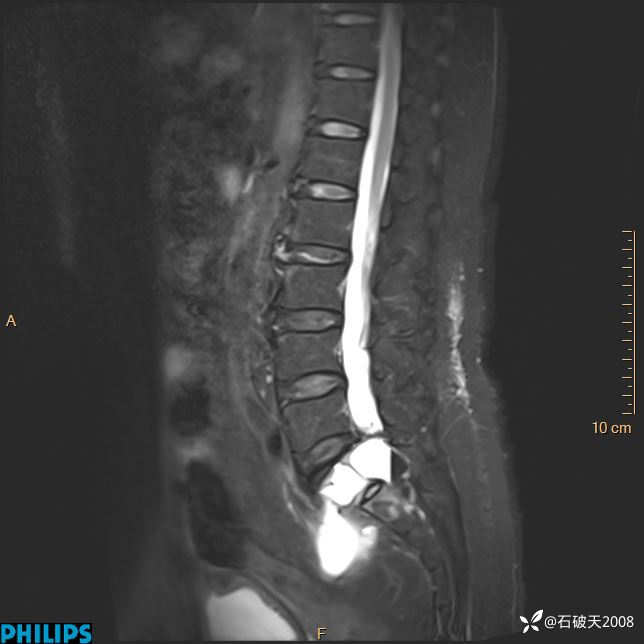

2023年3月份MRI影像

T1矢状位